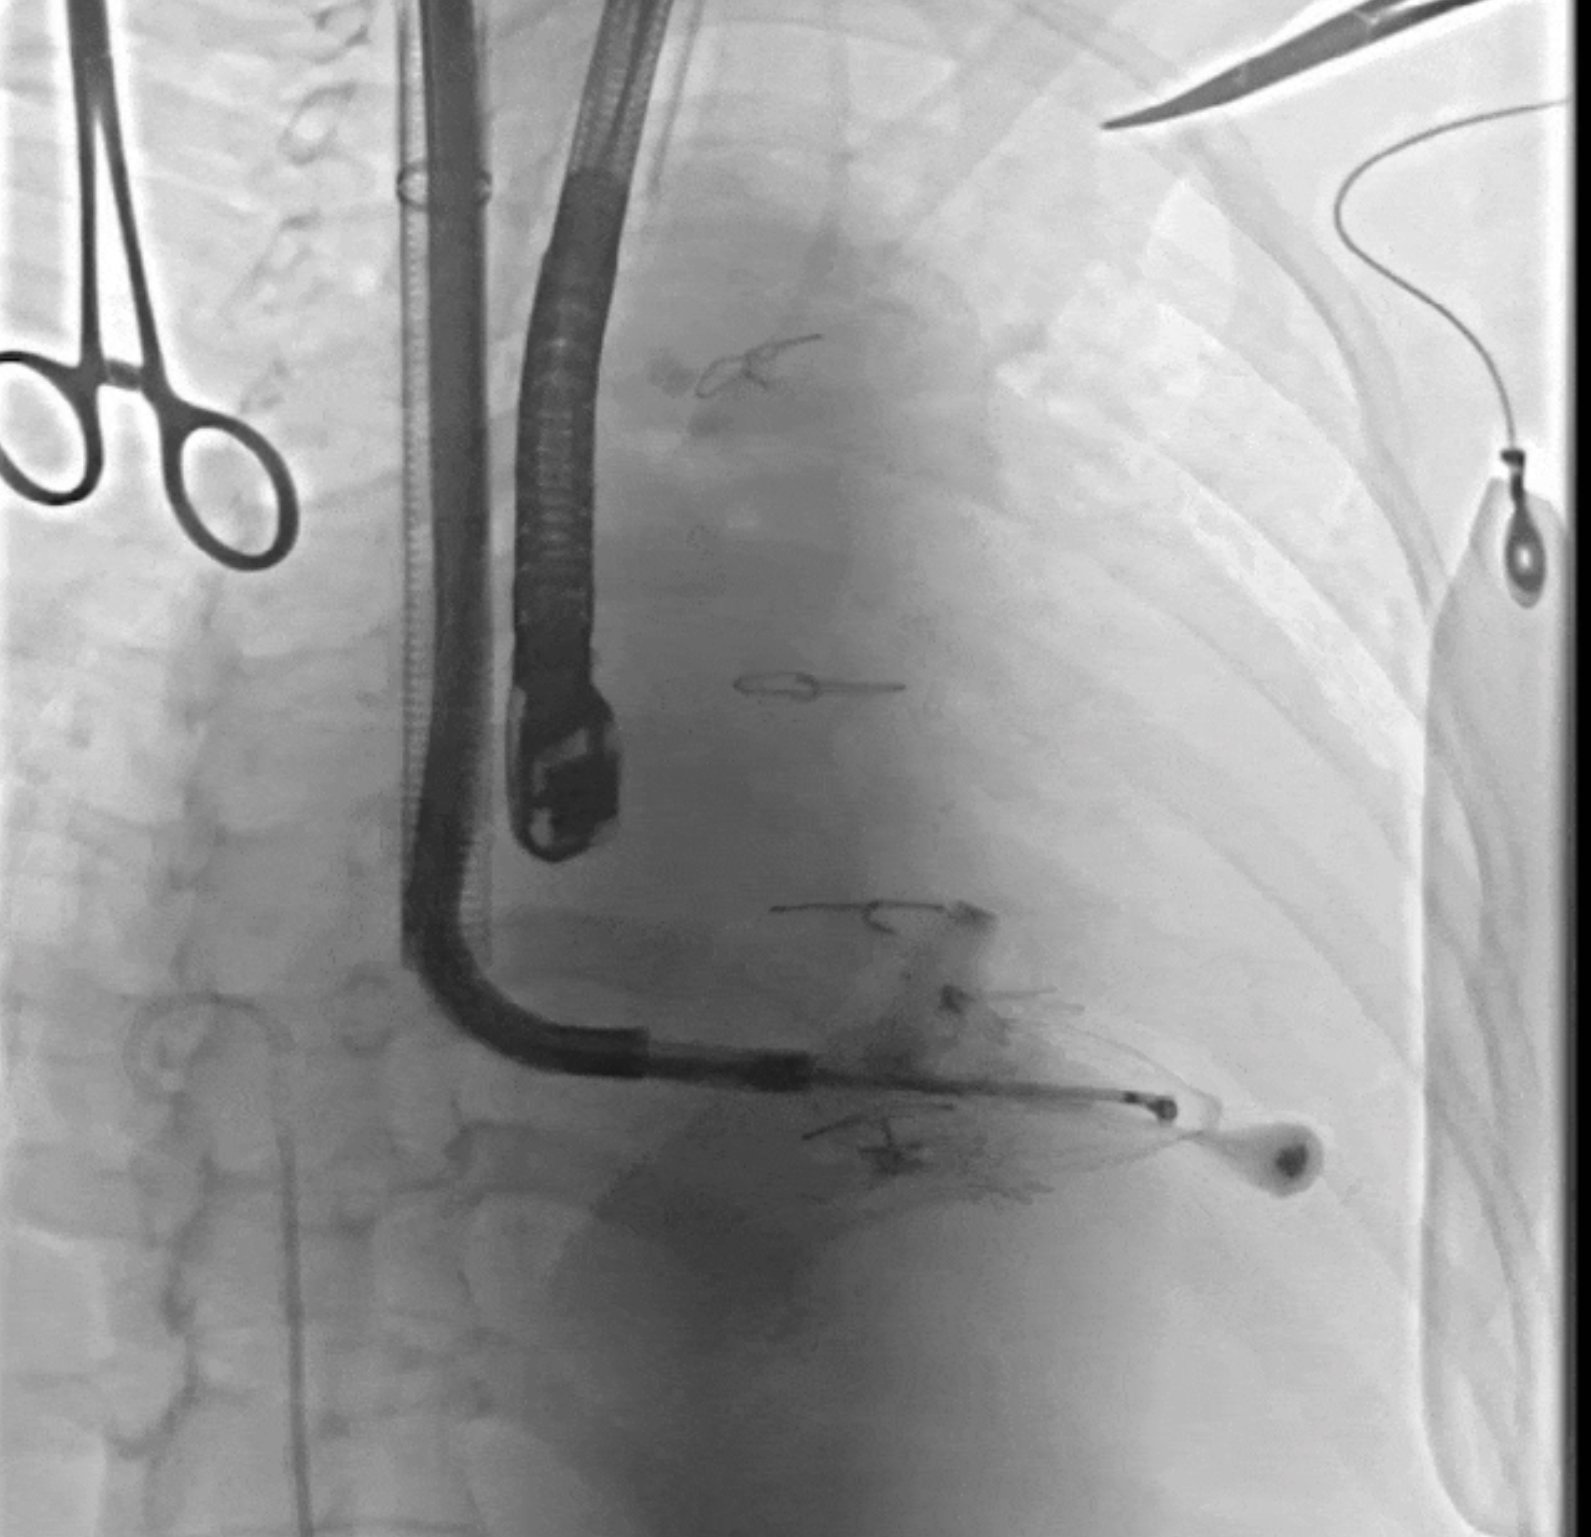

術(shù)中DSA所見(jiàn):經(jīng)LuX-Valve Plus輸送器系統(tǒng)五向調(diào)整,人工瓣膜同軸良好,夾持件均在瓣葉下。